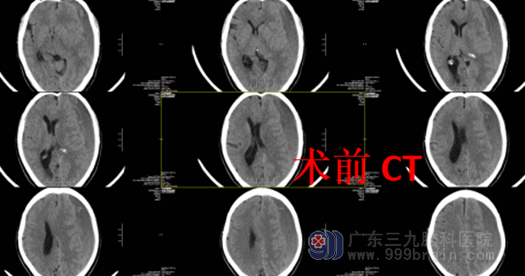

老百姓中有一种说法,老年人经不起摔。最近我们科室来了一位容爷爷,他4月余前不慎从家中摔倒致头部、右前臂轻外伤,受伤后昏迷约1分钟,到当地医院查头颅CT提示左侧额颞顶部硬膜下小血肿,住院保守治疗后症状好转出院,1周前患者出现右侧肢体乏力,在外院查头颅CT提示“左侧额颞顶部大面积慢性硬膜下血肿,中线结构右侧偏移”,家属要求转院至我院就诊,找到了广东三九脑科医院外十科主任——欧阳辉教授。